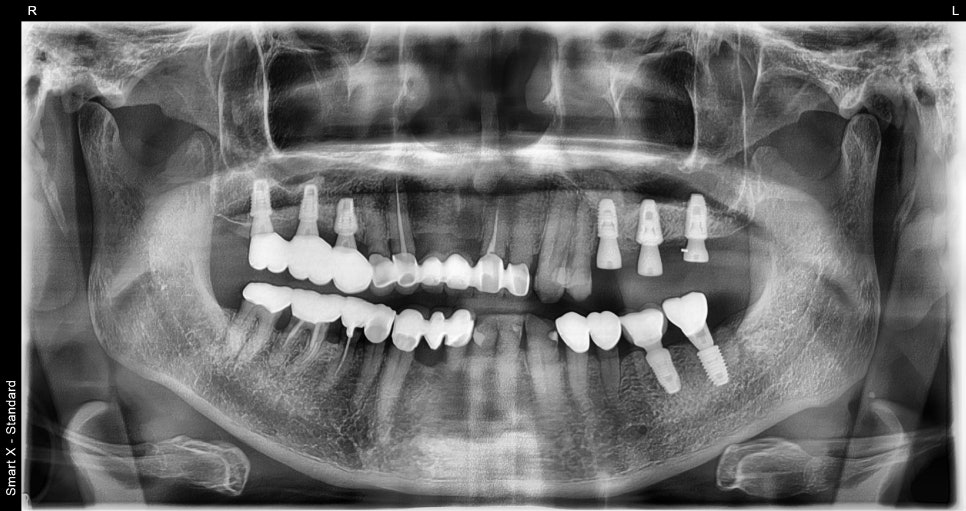

#25 발치 후 즉시 임플란트 식립 후 촬영한 파노라마 엑스레이입니다.

양 옆 치아에 맞춰 가지런히 잘 심겨진 모습입니다.

그리고 #26 27 임플란트 크라운 제거 후 단추(힐링 어버트먼트)로 안전하게 교체했습니다.